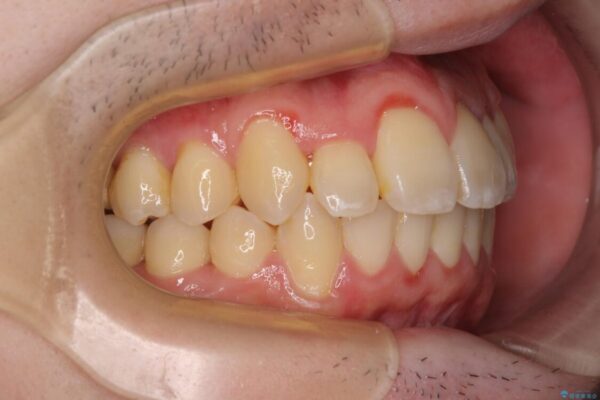

八重歯や奥歯の噛みにくさを気にして来院された患者様です。

前歯のクロスバイトや八重歯の他に、左右最後臼歯のシザーズバイト(鋏状咬合)が認められました。

治療前